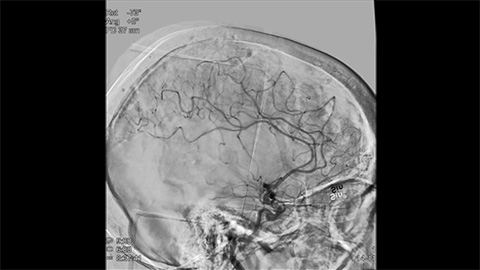

Klinische Anwender verlassen sich auf die klassische DSA-Bildgebung als wichtigste Informationsquelle während des gesamten Eingriffs.

3D-RA liefert in wenigen Sekunden eine volumetrische Darstellung und unterstützt so die Beurteilung von Position, Größe, Hals und Schweregrad des Aneurysmas für die Behandlungsplanung. Darüber hinaus bietet 3D-RA Volumendaten mit hoher räumlicher Auflösung und gleicht Patientenbewegungen automatisch aus.